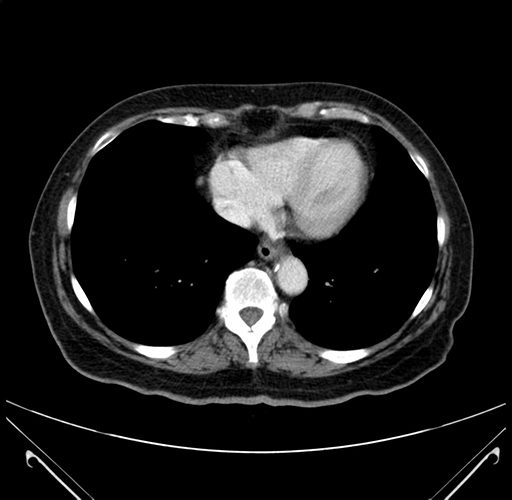

Pre-Chemo: Axial Venous